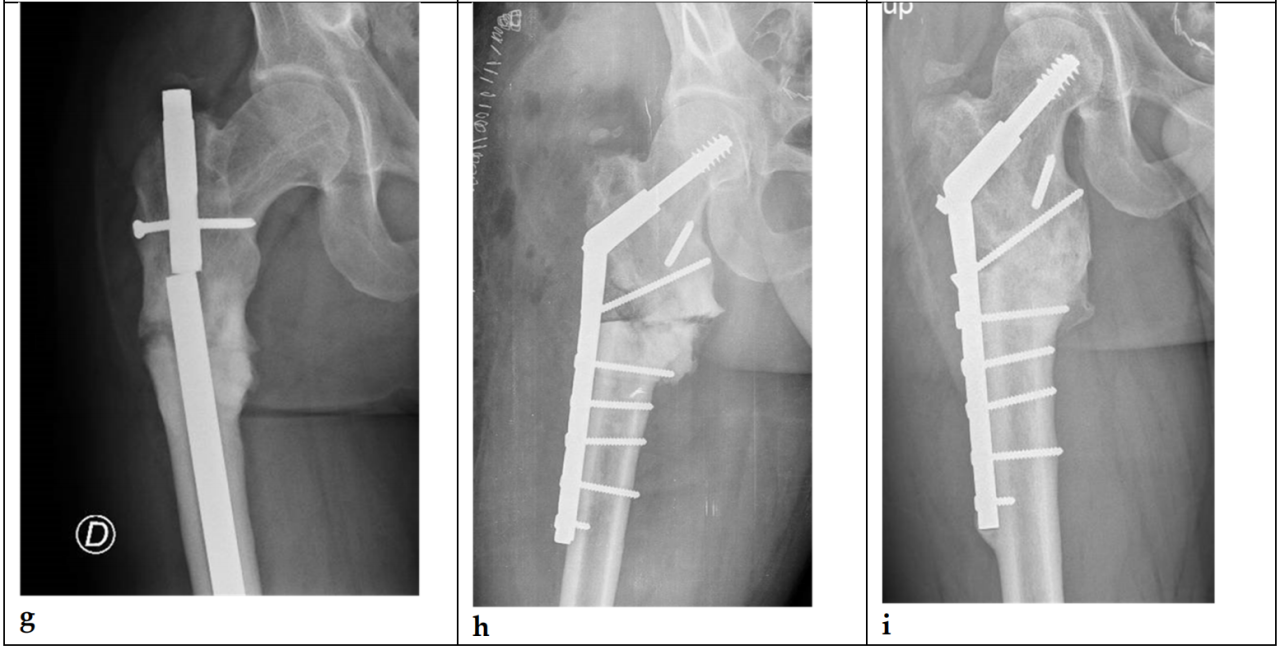

Goodnough等人比较了TFNA与其前代产品——股骨转子间固定髓内钉(Trochanteric Fixation Nail, TFN; DePuy Synthes, Synthes, Oberdorf, Switzerland)的翻修风险。他们发现,TFNA的总体翻修率与早期TFN相似,两组中内植物断裂均为罕见的翻修原因。这些作者发现,TFNA与因不愈合而进行翻修的风险更高相关(风险比[HR]为1.86 [95%置信区间(CI), 1.11 至 3.12]; p = 0.018)。TFNA的总体翻修率与早期TFN相似,两组中内植物断裂均为罕见的翻修原因[16]。最后,Swift等人比较了Synthes TFN和Zimmer Natural Nail(ZNN)。未发现TFN与ZNN结构在失败率或失败模式上存在差异[17]。图2展示了一例采用股骨转子间固定髓内钉(TFN; DePuy Synthes, Synthes, Oberdorf, Switzerland)固定的股骨转子间骨折。

图2. (a-i). 35岁男性股骨转子间骨折(ITF)(a);采用股骨转子间固定髓内钉(TFN;DePuy Synthes, Synthes, Oberdorf, Switzerland)进行固定 (b);术后18个月X光片显示骨折未愈合 (c)(d);实施了更换髓内钉及植骨手术 (e);12个月后仍未实现愈合 (f)(g);遂采用刀片钢板结合植骨进行新的固定 (h);24个月后影像显示最终实现了骨愈合 (i)。